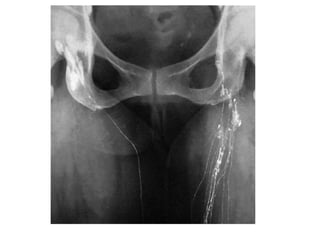

• Lymphangiography

INVESTIGATION OF LYMPHOEDEMA • ‘Routine’tests • Lymphangiography • Isotope lymphoscintigraphy • Computerised tomography • Magnetic resonance imaging • Ultrasound • Pathological examination